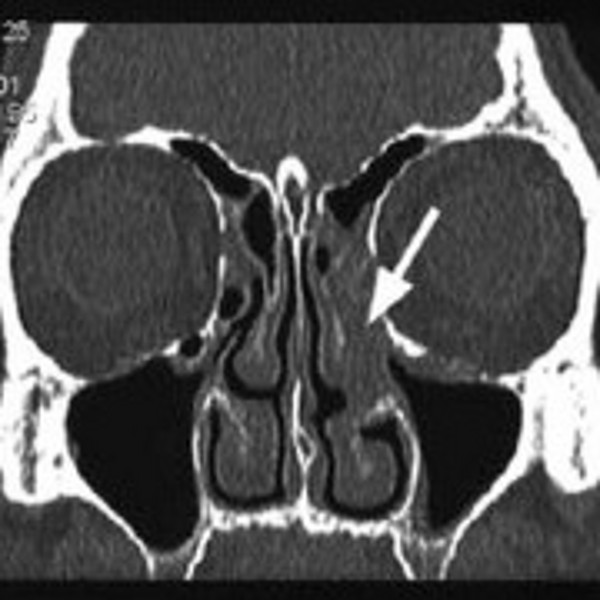

Die Sinusitis ist ein entzündlicher Prozess, der die Schleimhäute einer oder mehrerer Nasennebenhöhlen (NNH) involviert. Bei der chronischen Sinusitis werden Störungen der Ventilation und Drainage der NNH durch Engstellen im Bereich der Zugangswege zu den Nasennebenhöhlen verursacht. Durch eine Nebenhöhlenoperation werden diese Engstellen behoben, so dass die Belüftung und Drainage der Nebenhöhlen wieder hergestellt werden.

Die Nebenhöhlenoperation wird immer in Vollnarkose und in der Regel durch die Nase mit starren Optiken oder dem Mikroskop operiert, so dass keine Narben im Gesicht entstehen. Da es sich um ein anatomisch anspruchsvolles Operationsgebiet handelt – die Nebenhöhlen grenzen an die Augenhöhle und das Gehirn – kann mit Hilfe der CT gesteuerten Navigation, welche bei uns in der Klinik routinemäßig verwendet wird, das Risiko für unerwünschte Verletzungen eben dieser Organe minimiert werden.